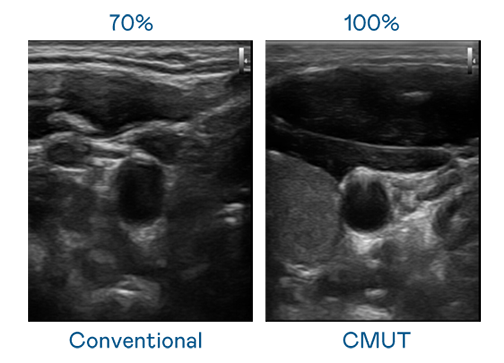

CMUT 技术是一种用电容式微机电元件来产生超音波讯号的技术。与传统 PZT 压电式技术相比,CMUT 频宽增加 30%,更宽频的超音波讯号让影像解析度大幅提升,是实现高影像品质医疗超音波扫描、促进精准医疗发展的关键技术。

大频宽带来超清晰影像

超音波影像的解析度高低,首先取决于探头能发出的讯号频宽。公海jcjc5500 CMUT 可提供高清晰的超音波讯号,提供高频宽、高灵敏度、影像纹理细节更高的超音波影像,协助医护人员缩短影像判读时间及利用精准的医疗影像进行诊断。